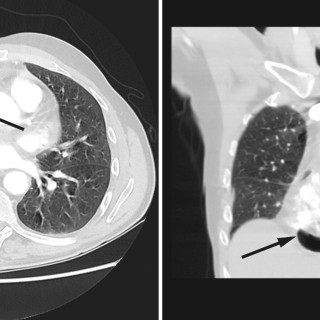

En yngre mann ble innlagt med venstresidige respirasjonsavhengige brystsmerter. Han hadde lett nedsatt allmenntilstand og feber. Det skulle bli et lengre sykehusopphold, der man diagnostiserte en uvanlig årsak til lungeaffeksjon. En tidligere frisk mann i slutten av tenårene ble via legevakt innlagt i sykehus etter ett døgn med venstresidige, respirasjonsavhengige smerter. Ved innkomst hadde han temperatur 37,6 °C, puls 117 slag/min, blodtrykk 104/57 mm Hg, respirasjonsfrekvens 24/min og perifer O2-metning på 94 % uten ekstra oksygentilførsel, og normale forhold ved klinisk undersøkelse...